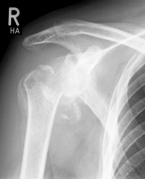

Special prostheses such as an inverse shoulder prosthesis (syn.: "Delta prosthesis", "Grammont prosthesis") for the combination of severe omarthrosis with joint instability and rotator cuff defects

Right: radiograph of an inverse shoulder prosthesis for rotator cuff defect arthropathy.